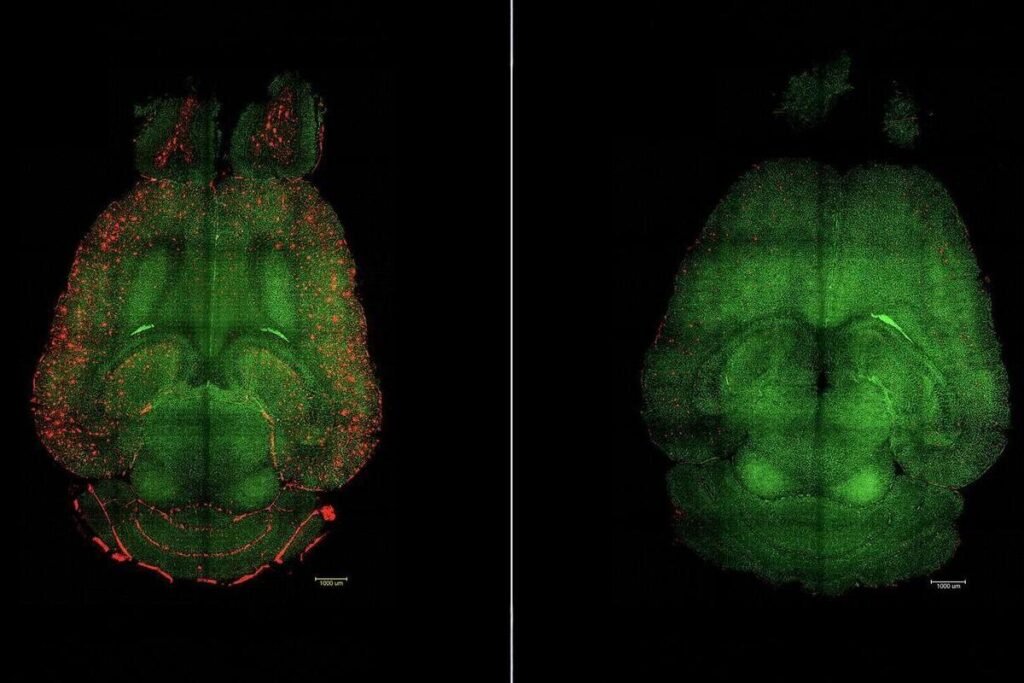

El principio del tratamiento no se centra directamente en las neuronas, sino en restaurar la función vascular del cerebro (la barrera hematoencefálica), lo que permite que las proteínas tóxicas que se acumulan en el Alzheimer puedan salir del tejido cerebral hacia la circulación sanguínea. En el caso de la proteína beta amiloide (Aβ), uno de los principales agentes implicados en la patología de Alzheimer, la acumulación se ve favorecida cuando el sistema de limpieza natural del cerebro deja de funcionar correctamente.

Según los datos del estudio, apenas una hora después de la inyección ya se observó una reducción del 50% al 60% en los niveles de Aβ en el cerebro de los ratones tratados. A lo largo del tiempo, los animales mostraron mejoras en su comportamiento cognitivo: por ejemplo, un ratón de 12 meses (equivalente a un humano de 60 años), tras seis meses de tratamiento, logró un comportamiento semejante al de uno sano, incluso al alcanzar una edad equivalente a un humano de 90 años (un año y medio).